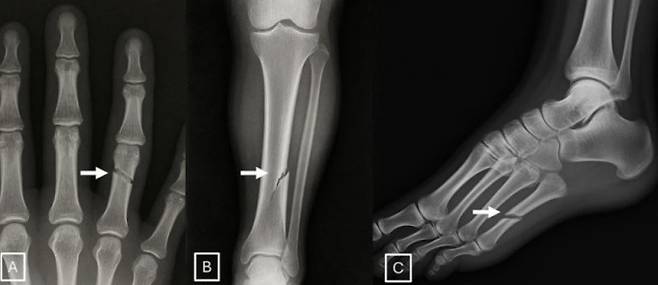

● 전문의도 속는 가짜 엑스레이 생성

AI가 만들어낸 가짜 의료 영상이 전문의조차 속이는 수준에 이르렀다는 연구도 나왔다. 미카엘 토르지먼 미국 마운트시나이 아이칸의대 영상의학과 교수 연구팀은 AI가 생성한 엑스레이 영상을 전문의가 얼마나 정확하게 가려내는지 시험한 결과를 국제학술지 '방사선학'에 24일(현지시간) 발표했다.

연구팀은 12개 의료기관 소속 영상의학과 전문의 17명에게 진짜 엑스레이와 챗GPT가 생성한 가짜 엑스레이를 섞어 보여줬다. 가짜가 섞여 있다는 사실을 알리지 않았을 경우 이상을 눈치챈 전문의는 41%에 그쳤다. 이후 가짜가 포함돼 있다고 알려준 뒤 다시 구별하게 했을 때도 정확도는 평균 75%였다. 경력 40년 베테랑과 신입 전문의 사이에 차이가 없었다.